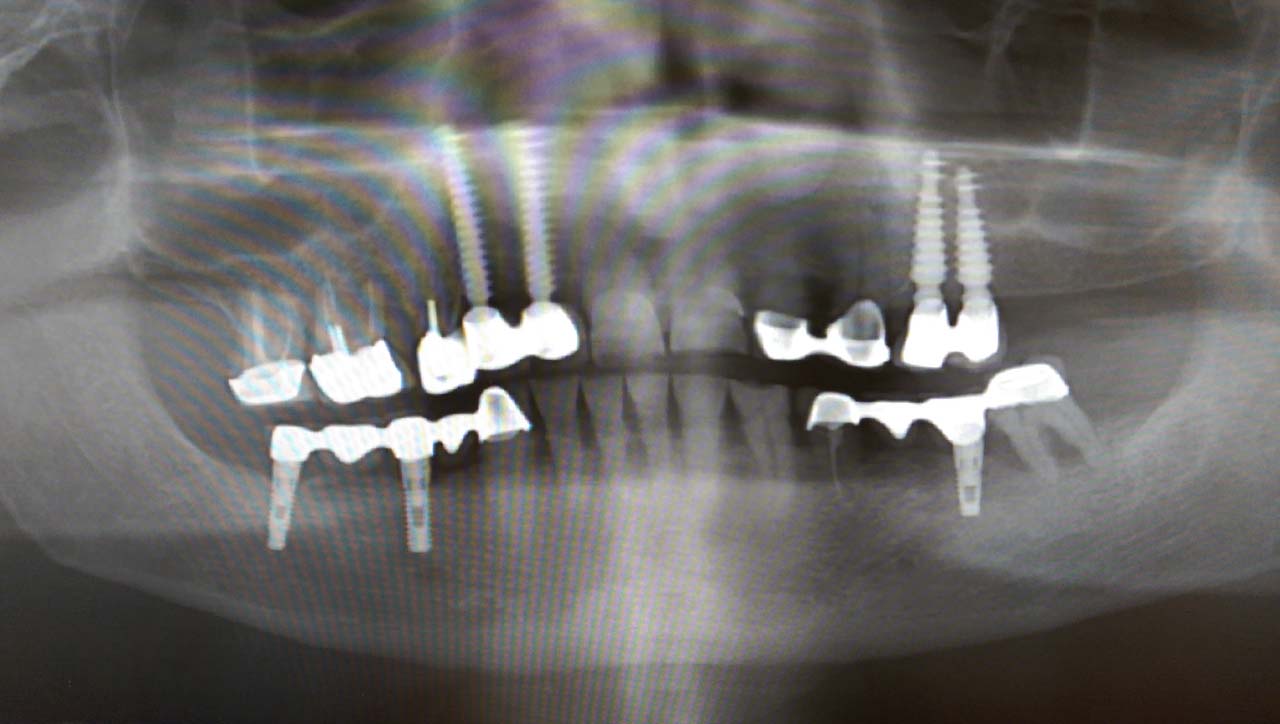

Teljes fogatlanság helyreállítása 2 nap alatt

Teljes fogatlanság helyreállítása 2 nap alatt azonnal terhelhető svájci IHDE implantátumokkal és PMMA műanyag hidakkal. Intraorális szkennerrel vettünk lenyomatot az implantáció után, és erre a digitális mintára készítette el a fogtechnika a hidak digitális tervezését, majd faragta ki műanyagból. Ezt a gyors munkát az azonnal terhelhető implantátumok és a digitális lenyomat, tervezés segítségével tudtuk megcsinálni mindössze 2 nap alatt. Dr. Kelemen Péter és a Symbion Fogtechnika munkája.